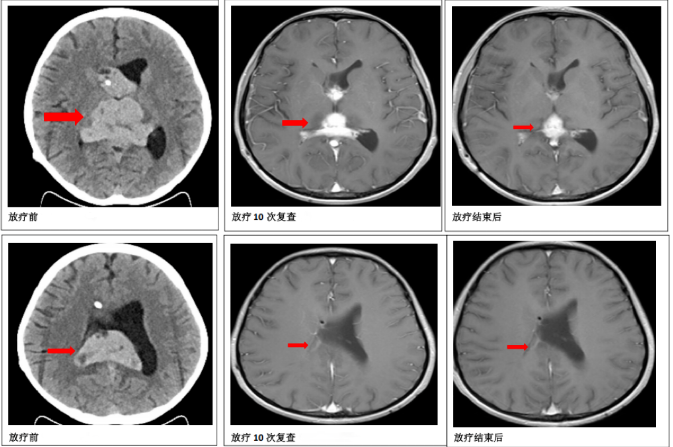

放疗10次后,医生再次给患儿做了颅脑核磁共振检查,和之前的检查结果对比发现,颅内的肿瘤明显缩小了,说明治疗效果很好,对放疗敏感,临床可以诊断为颅内生殖细胞肿瘤,可按颅内生殖细胞肿瘤的放疗计划继续放疗。为了减少放疗可能带来的副作用,肿瘤科一病区放疗医师根据新的检查结果重新调整了放疗方案,这样既能有效控制肿瘤,又能减少对患儿的伤害。